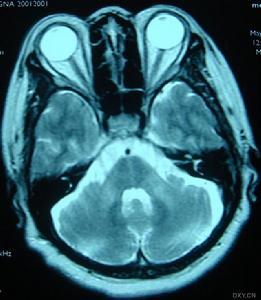

1、CT或MRI顯示小腦萎縮很明顯,有時可見腦幹萎縮;腦幹誘發電位可出現異常,肌電圖顯示周圍神經損害;腦脊液檢查正常。

根據共濟失調、構音障礙、錐體束征等典型共同症狀,以及伴眼肌麻痹、錐體外系症狀及視網膜色素變性等表現,結合MRI檢查發現小腦、腦幹萎縮,排除其他累及小腦和腦幹變性病可臨床確診。然而,臨床僅根據各亞型特徵性症狀、體徵確診仍不準確(SCA7除外),可用PCR法準確判定洲型及CAG擴增次數,進行基因診斷。